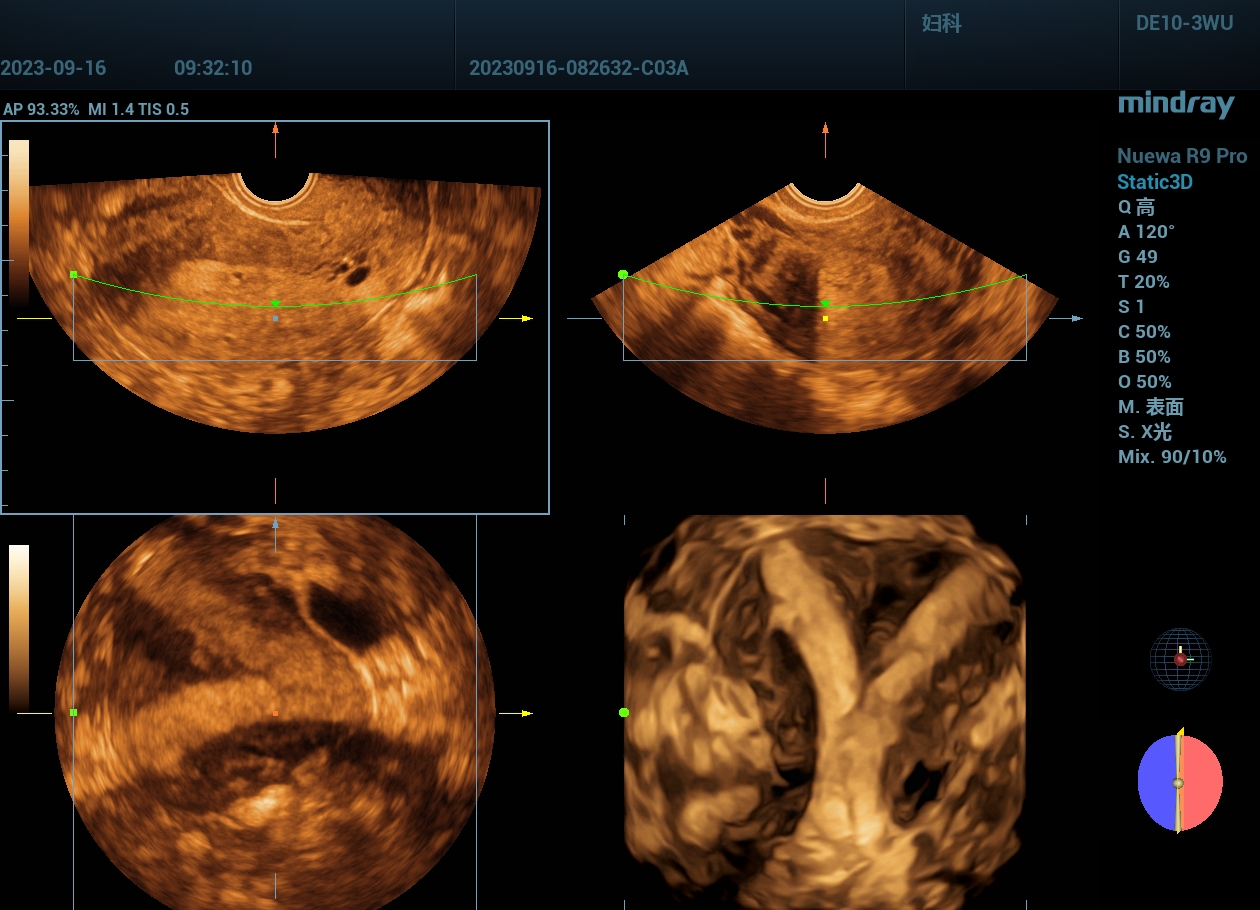

病例,弓形子宫1:宫腔形态异常,二维加三维

www.jinrichaosheng.com